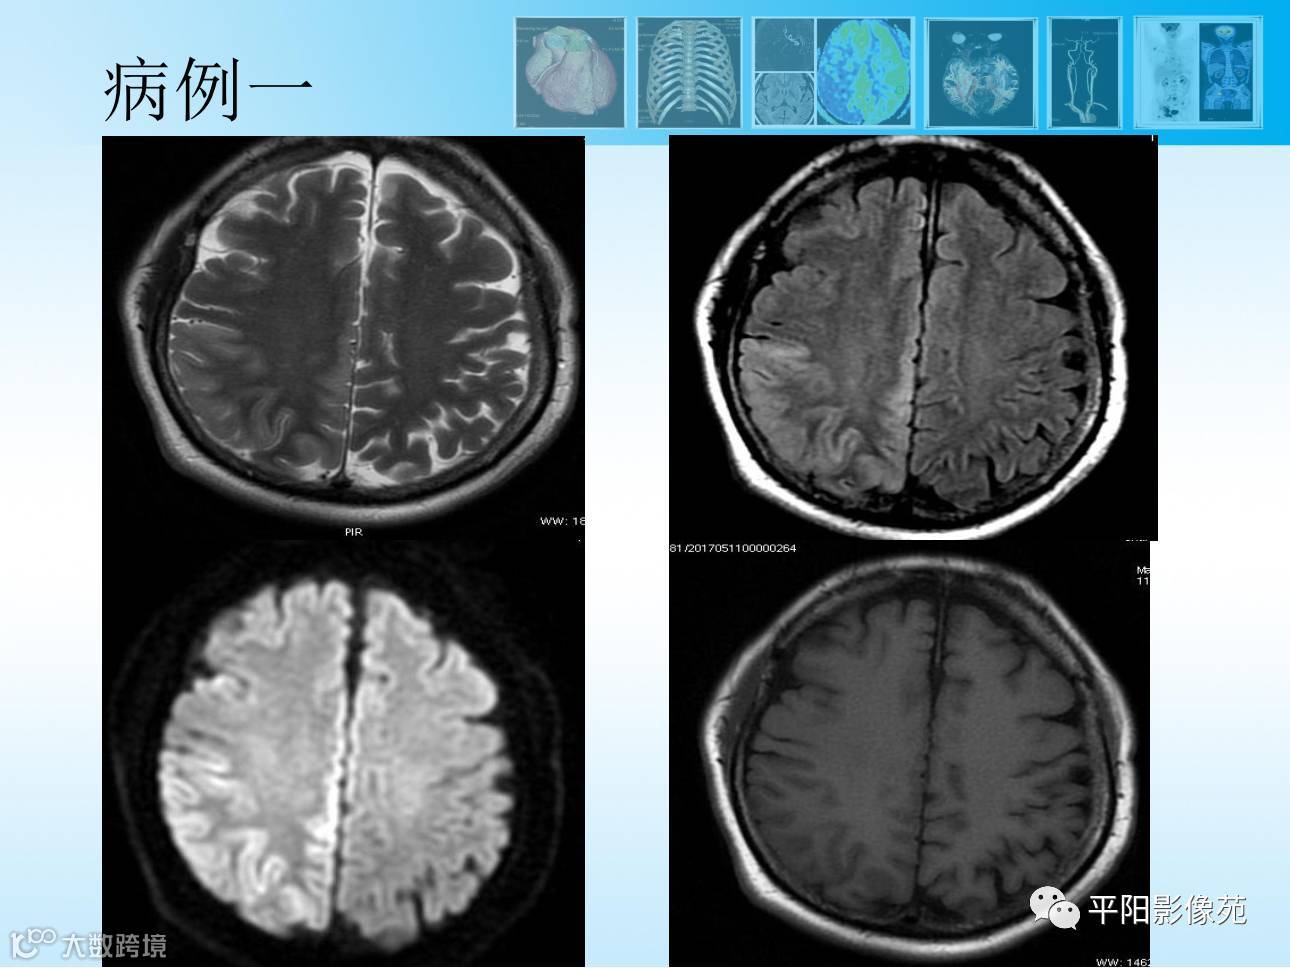

【MR功能成像专题2】3D-ASL灌注成像篇

导读:动脉自旋标记ASL成像,是一种完全无创的、不需注射造影剂的灌注成像方法,临床应用广泛。